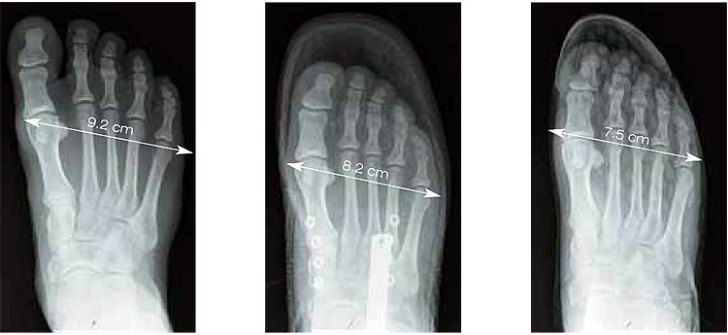

Piede senza scarpa

Piede con scarpa sportiva

Piede con scarpa normale